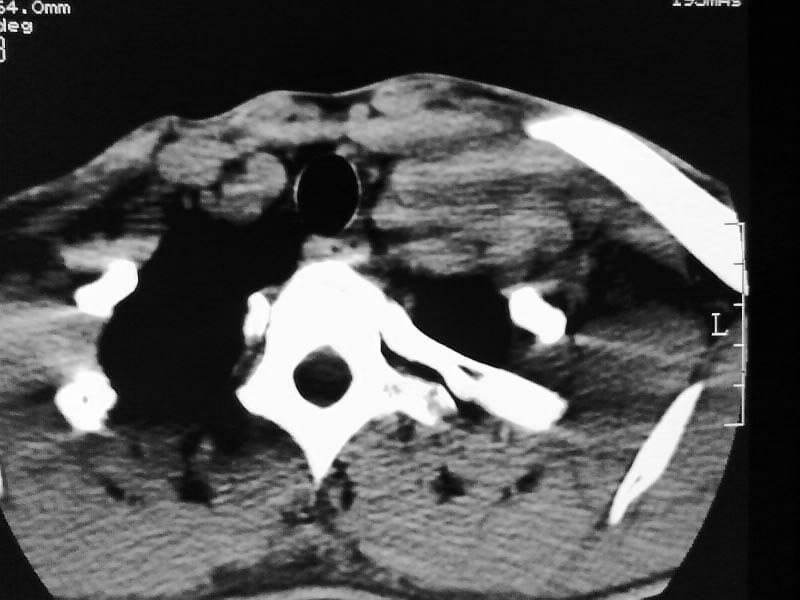

以下是引用余辉在2009-5-3 11:36:00的发言:[br]左侧胸锁乳突肌下方不规则肿物影,边界不清,内部密度不均,左侧颈外侧区脂肪增多,多发淋巴结肿大,考虑淋巴或神经来源肿瘤可能性大,不除外淋巴结炎,肌源性肿瘤及增生性肌炎等,活检